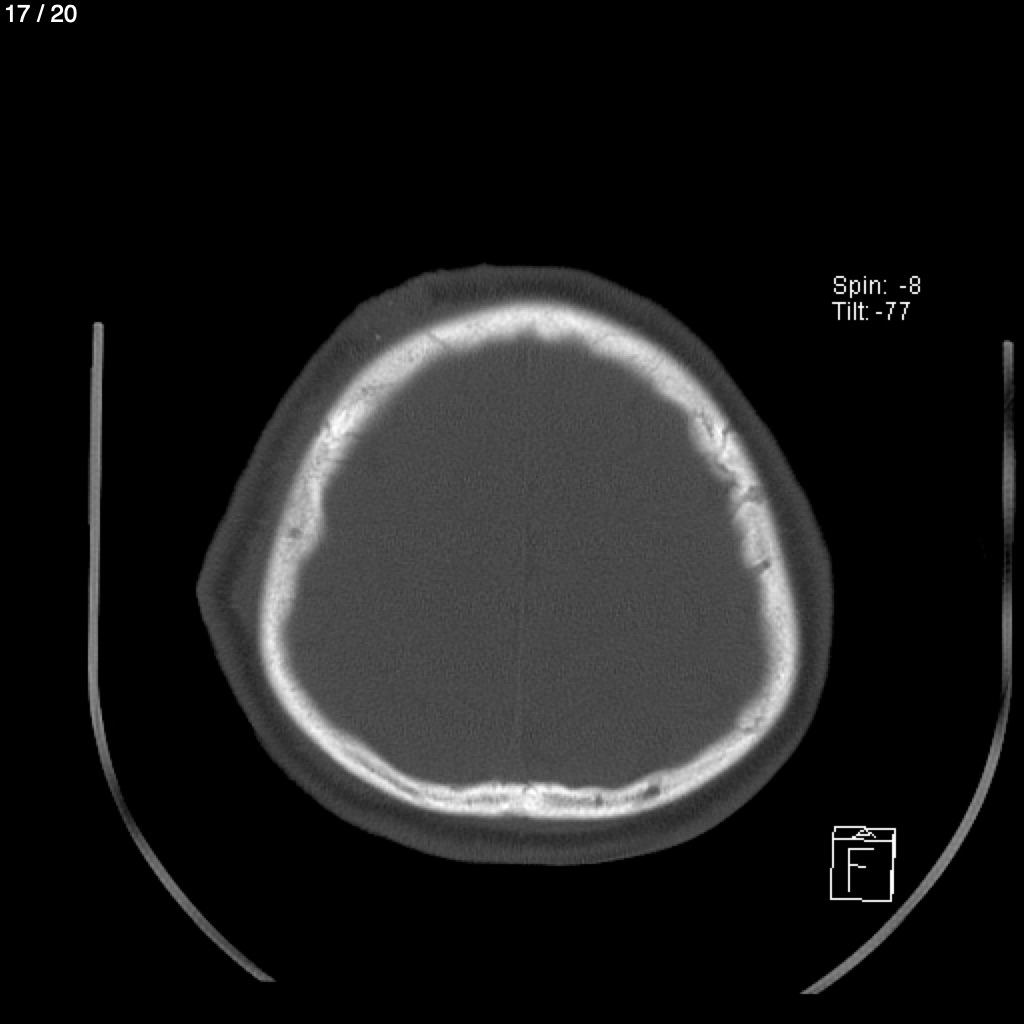

Home A​l​e​x​a​n​d​e​r​ ​D​e​ ​J​e​s​u​s​ ​P​a​z​ ​G​a​r​c​i​a​ ​-​ ​C​a​b​e​z​a​ ​C​r​a​n​e​o​_​S​y​c​ ​(​A​d​u​l​t​o​)